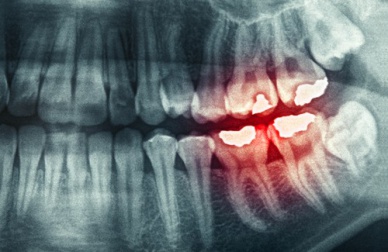

A lungo andare questo stringere o digrignare i denti può causare:

- Problemi all’articolazione temporo-mandibolare

- Infiammazione dei muscoli di questa zona

- Usura prematura dei denti

- Fratture dentali

- Perdita dello smalto dentale

- Eccessiva sensibilità nei denti